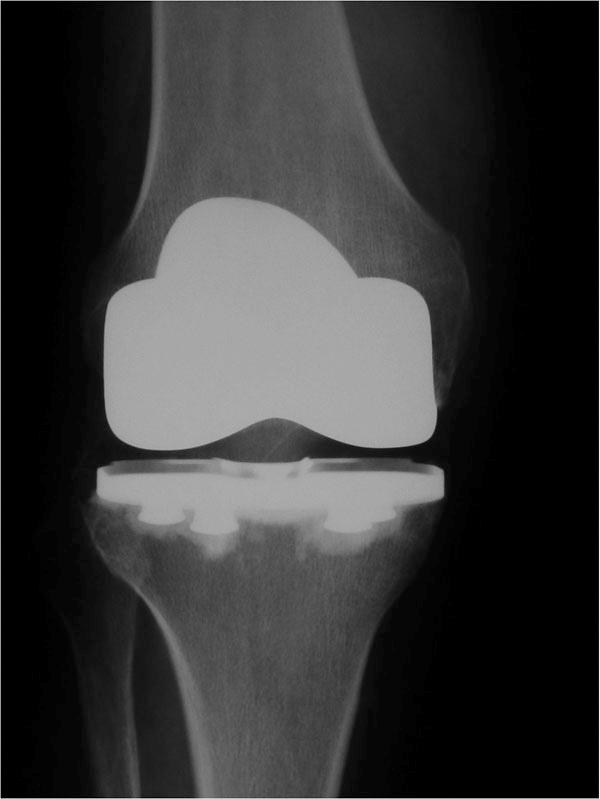

Total or Partial Knee Replacement

Once non-operative measures have failed, discussion about knee replacement is appropriate. While there are risks to a knee replacement, results are generally excellent and the knee can routinely last for many years. The longevity of the knee replacement is related to the activity level a patient. For this reason, running or hard labor on a knee replacement is not advised.

There are knee several types of knee replacements. If only one part of the knee (usually the inner or medial compartment) is severely involved with arthritis and the other compartment (especially the lateral compartment) is normal, a partial knee replacement (unicondylar knee replacement or ‘uni’) may be the best answer. If the whole knee is worn down to bare bone surfaces and there is significant pain, a total knee replacement (total knee arthroplasty) may be indicated.

Newer minimally invasive knee replacements may offer an advantage to older more invasive approaches. Knee replacement, however, is an elective procedure — patients usually know when this level of treatment is necessary.